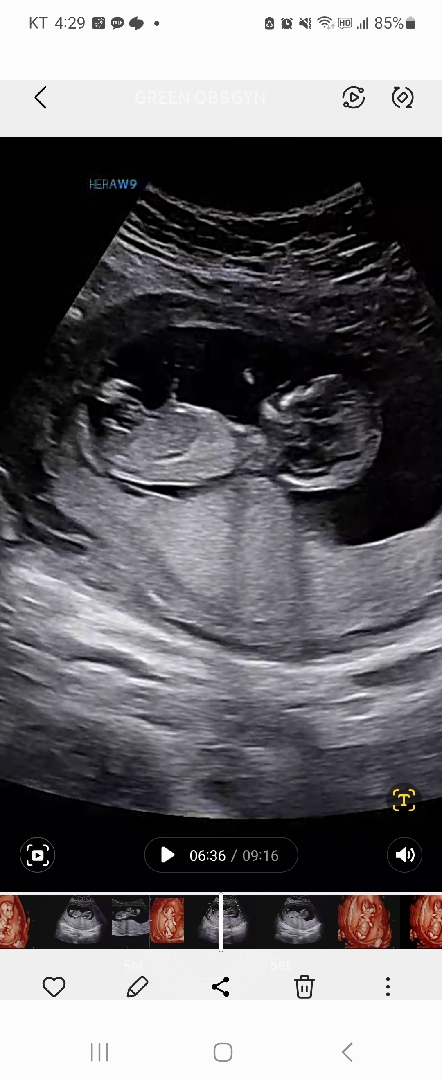

12주3일차 초음파 각도법 투표해주세요🙏

14살 차이 나는 둘찌가 생겼는데 둘째다 보니 성별이 너무 궁금하네요 ㅋㅋ 다들 의견 부탁드려요!

14주3일차 병원다녀오니 남아였어요 ~~ 투표 감사합니다 ㅎㅎ